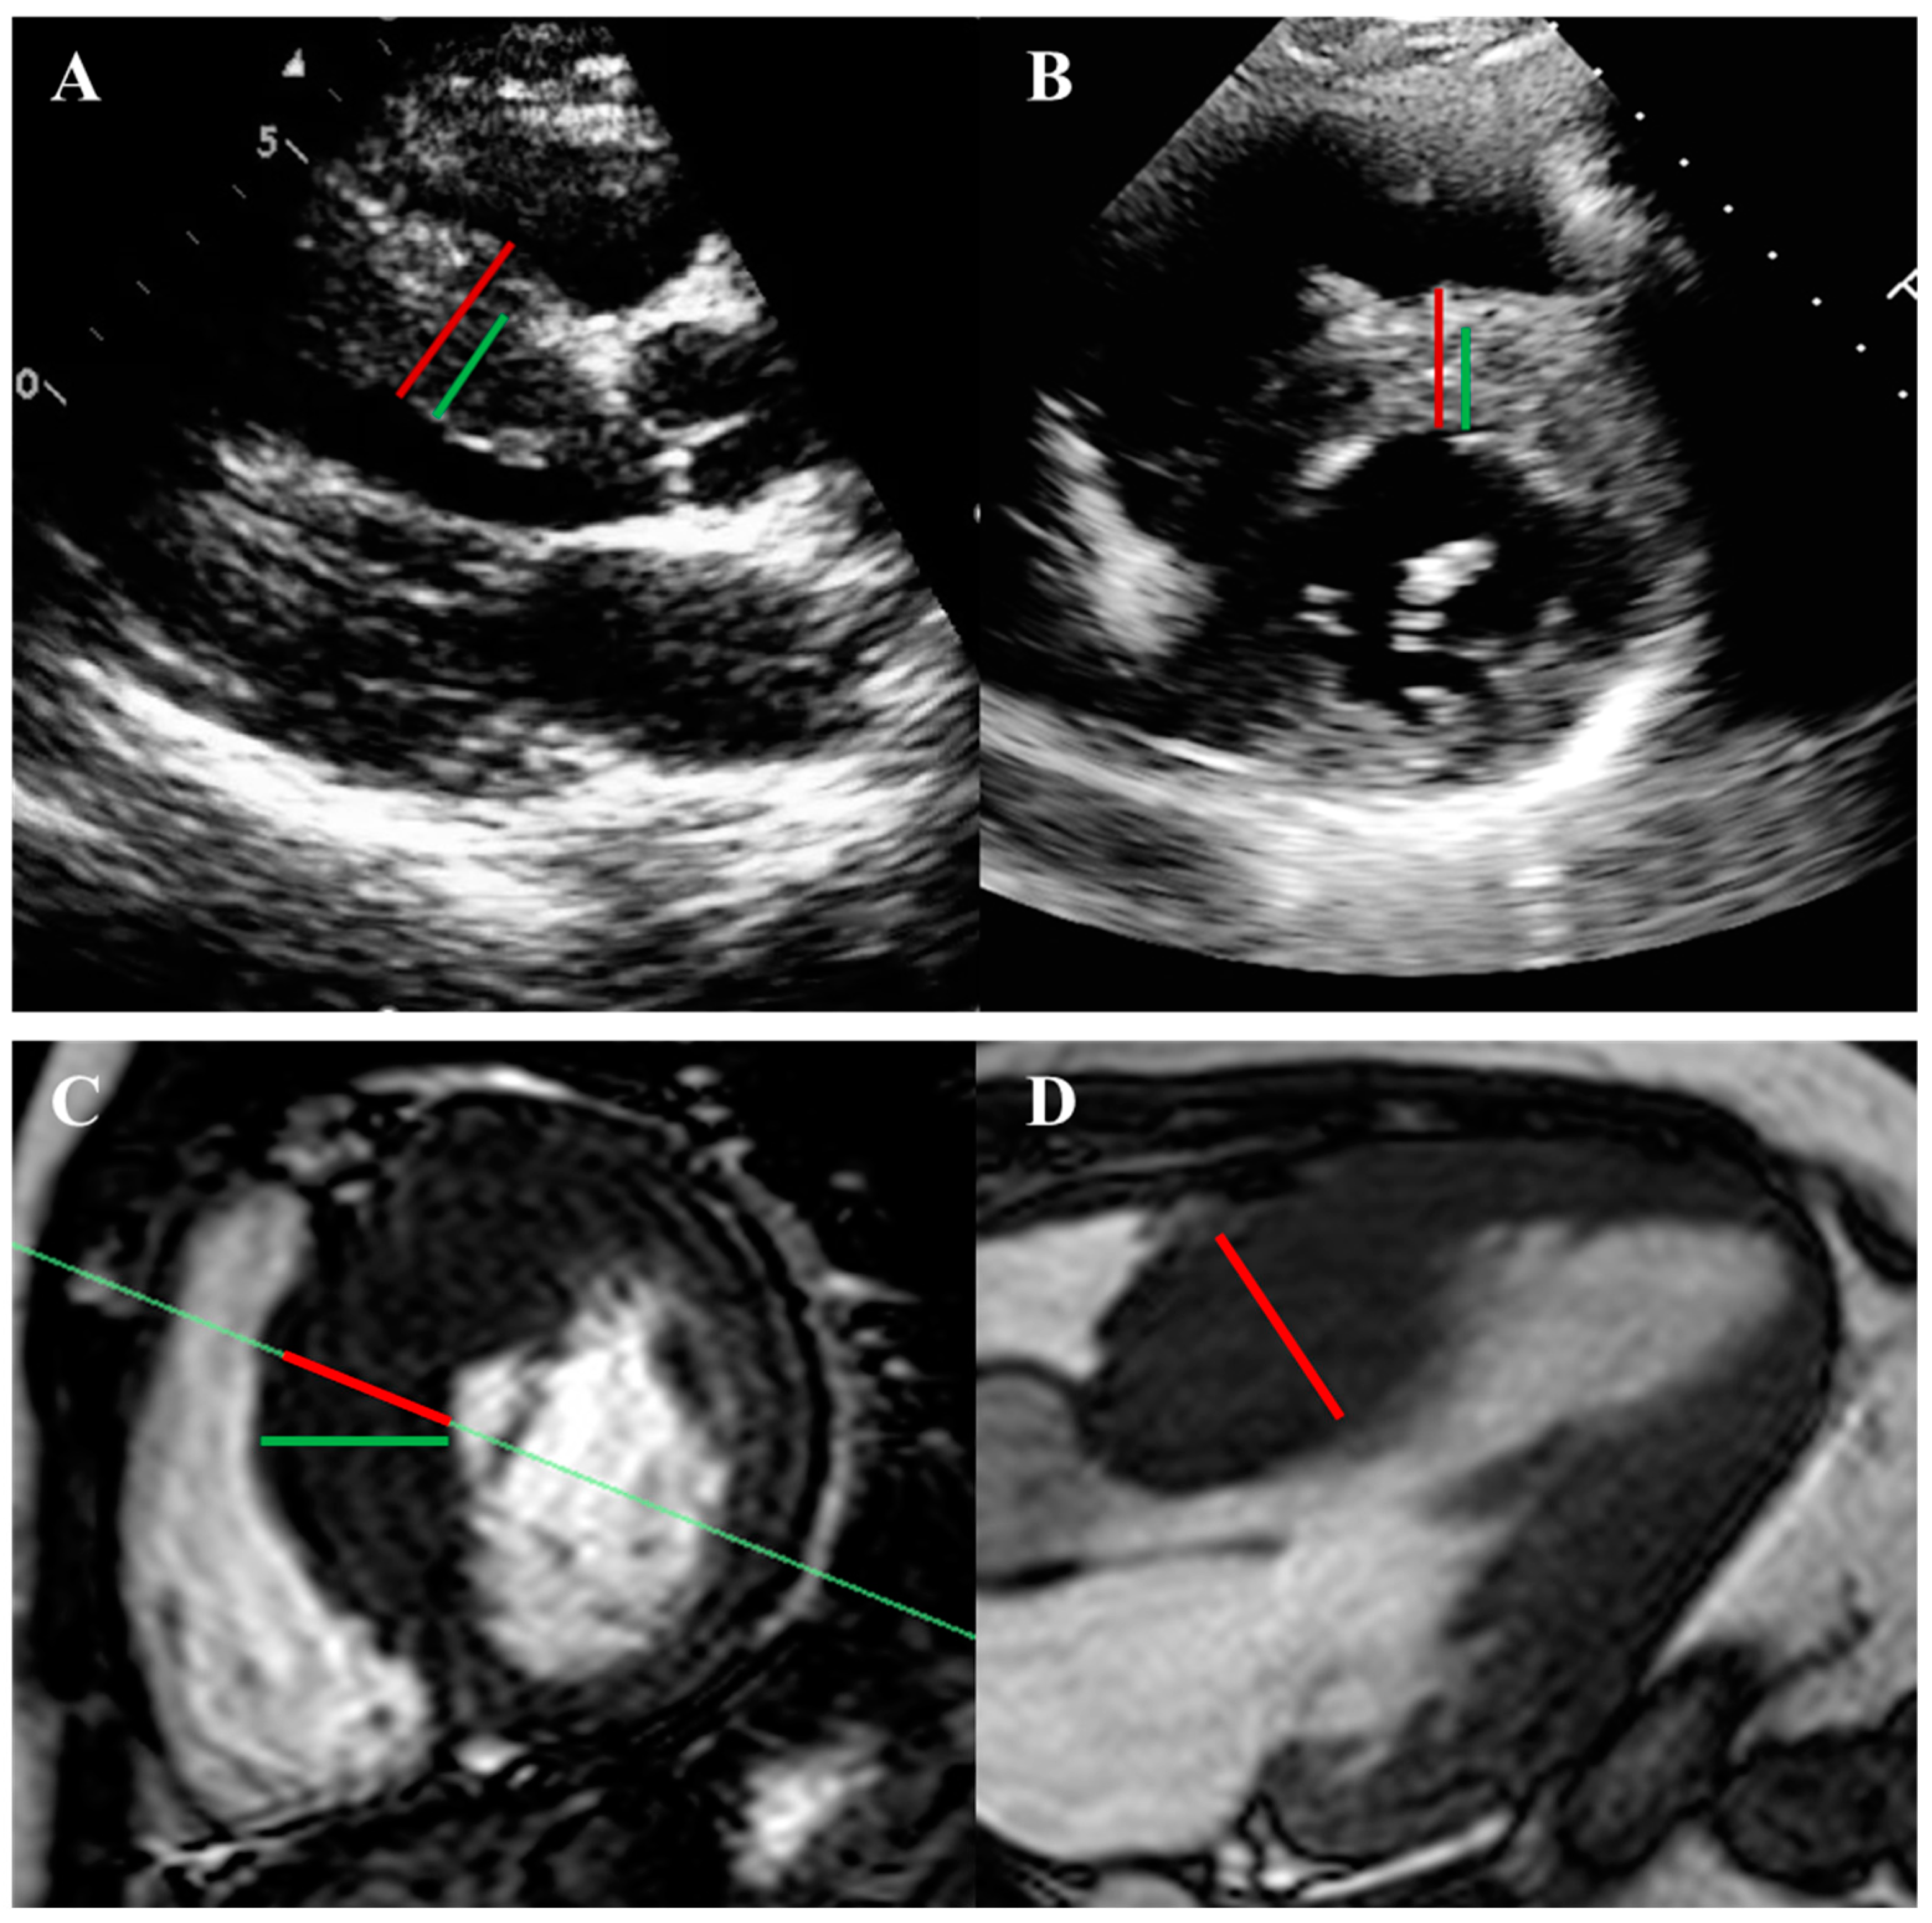

2.1. Left Ventricular Hypertrophy and Morphology

3.1. Echocardiography

3.3. Cardiac Magnetic Resonance Imaging